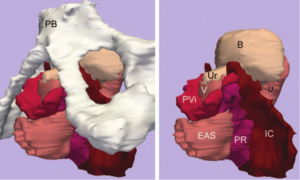

- 4.39 Using Stress MRI to Analyze the 3D Changes in Apical Ligament Geometry from Rest to Maximal Valsalva: A Pilot Study